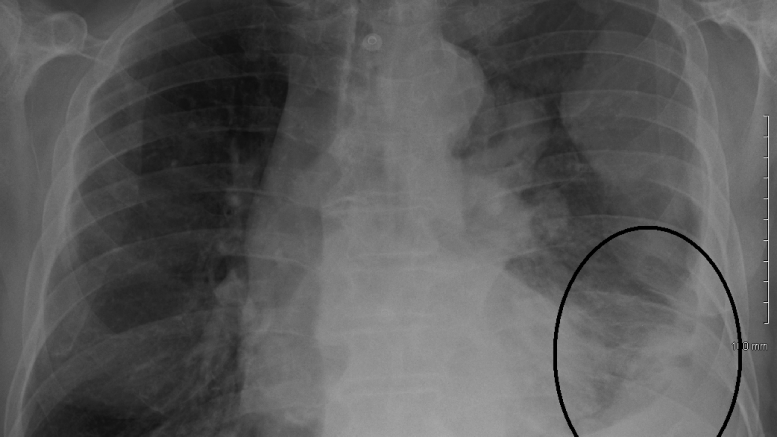

Snowman coloring sheet. Mesothelioma is a type of cancer that develops from the thin layer of tissue that covers many of the internal organs known as the mesothelium. The most common area affected is the lining of the lungs and chest wall. The average life expectancy is 12 21 months after diagnosis but prognosis may improve with treatment.

Asbestos is the main cause of mesothelioma. This type of cancer makes up 70 to 80 of all mesotheliomas. Cancer can also start in the peritoneum which is called peritoneal mesothelioma.

The american cancer society is a qualified 501c3 tax exempt organization. It usually starts in the pleura which is called pleural mesothelioma. This type of cancer makes up about 25 of all mesotheliomas.

Less commonly the lining of the abdomen and rarely the sac surrounding the heart or the sac surrounding the testis may be affected. All these symptoms can be caused by other common conditions other than cancer but its important to go to the gp and get any unusual changes checked out especially if youve been exposed to asbestos in the past. Cancer society volunteering information and supportive care services.